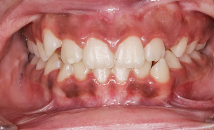

✅ 7. 잇몸이 약간 내려앉은 느낌

잇몸이 조금씩 내려가면 치아 뿌리가 노출되기 시작하고,

치은염이 심화되면 치주염으로 이어져 치아가 흔들리거나 빠질 수 있어요.

| 위험 신호 |

- 치아가 길어 보이고 뿌리가 드러난다

- 치간칫솔을 사용할 때 출혈과 통증이 반복된다

- 잇몸이 점점 얇아지고 움푹 패인 느낌